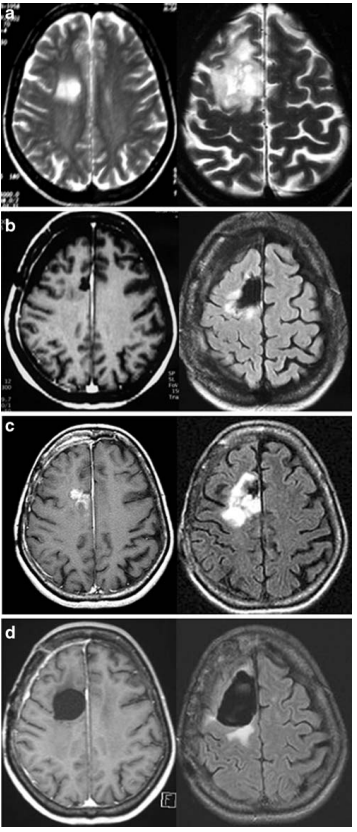

11例患者术前MRI显示注射钆后增强(图1和2)。患者术前肿瘤体积为30毫升(范围为5至130毫升)。

图1

术前MRI增强与病理检查的比较表明,11例肿瘤去分化患者中有10例增强,8例无肿瘤去分化患者中有1例增强。这一差异具有统计学意义(p<0.05)。